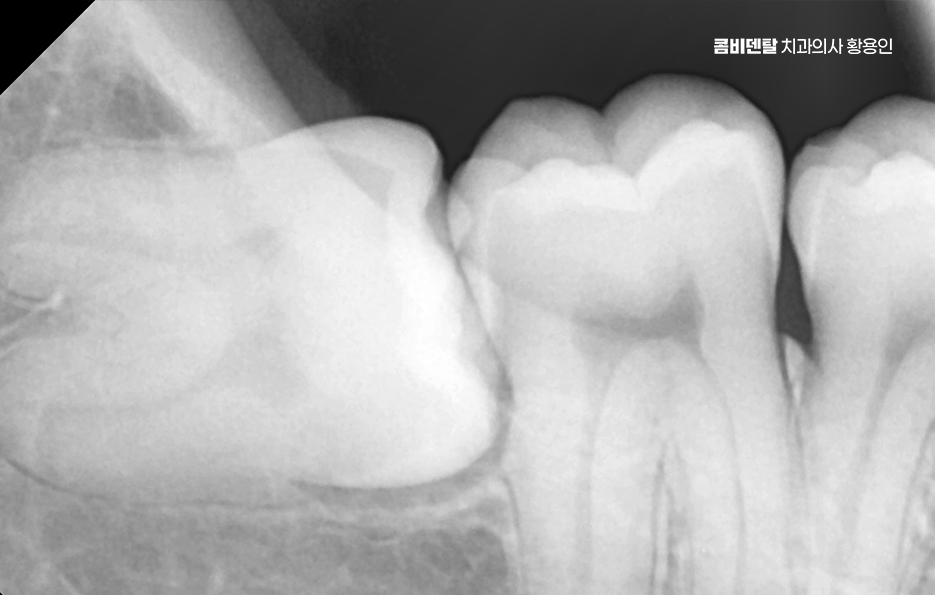

출처 아카이브 열기완전매복사랑니라는 단어 자체가 참 낯설게 느껴졌어요, 처음에는 그게 무슨 말인지조차 몰랐고, 단순히 사랑니라는 건 그냥 어금니 맨 끝에 나중에 나오는 이 정도로만 알고 있었어요 누구나 한 번쯤은 뽑는 거니까 나한테도 언젠간 그런 일이 생기겠지 하면서도, 사실 딱히 깊이 고민해본 적은 없었어요, 그런데 어느 날 왼쪽 아래 턱 깊숙한 곳이 묘하게 욱신거리고, 무언가 불편한 느낌이 계속되더라고요, 딱히 부어오르거나 겉으로 드러난 문제는 아닌데, 먹을 때마다 이상하게 한쪽으로는 씹기 싫고, 가만히 있을 때도 잇몸 깊은 곳에서 묵직한 압력이 느껴지는 기분이었어요, 그게 몇 주째 반복되니까 이제는 그냥 넘길 수 없겠다는 생각이 들어서 치과에 가게 됐어요. 진료를 받고, 엑스레이를 찍고, 설명을 듣는데, 그제야 알게 된 게 바로 완전매복사랑니라는 이름이었어요, 내 사랑니는 겉으로는 전혀 드러나지 않았지만, 잇몸과 뼈 안쪽 깊숙이 누운 채로 누워 있었고, 그것도 똑바로 난 게 아니라 옆 어금니 방향을 향해 비스듬히 자라고 있다는 것이었죠. 문제는 사랑니 발치도 까다로울 수 있고 주변 치아나 잇몸에도 영향을 줄 수 있다는 점이었어요

완전 매복사랑니는 보통 아래턱, 즉 하악의 뒤쪽에서 자주 발견되는데 위턱보다는 아래턱 뼈가 더 단단하고 구조적으로 복잡해서 발치 난이도가 더 높을 수 있으며 이 매복된 사랑니는 위치나 각도에 따라서도 발치의 난이도가 달라질 수 있었어요

여기에 더해서 신경과의 거리도 문제로 아래턱에는 하치조신경이라는 굵은 감각신경이 지나가는데 완전 매복사랑니의 뿌리가 이 신경과 가까이 위치해 있는 경우가 많아서 만약 발치 중 이 신경을 건드리거나 손상이 생기면, 입술이나 턱 끝 부위에 감각 이상이 생길 수 있어요.

완전매복사랑니 발치 그래서 무조건 바로 뽑는다고 되는 게 아니라, 사전에 정밀한 진단과 영상검사가 꼭 필요하며 일반적인 파노라마 사진 외에도 CT 촬영을 통해 신경과의 거리, 뿌리의 형태, 턱뼈의 두께 등을 정밀하게 확인해야 발치 계획을 안전하게 세울 수 있었어요.